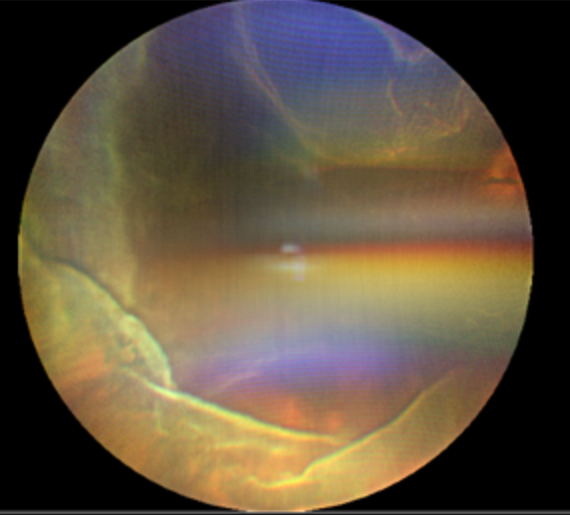

顾名思义,这个病至少包含两个表现:视网膜脱离和脉络膜脱离。1. 视网膜脱离:视网膜是眼球最内层的一层透明薄膜,相当于相机的底片。当它因为视网膜裂孔从依附的壁上“脱下来”时,就形成了孔源性视网膜脱离。患者通常会感到眼前有黑影遮挡,有闪光感、飞蚊症,脱离累及视网膜最重要的结构——黄斑中心凹时,视力会急剧下降。2. 脉络膜脱离: 脉络膜是位于视网膜和眼白(巩膜)之间的一层富含血管和色素的组织,负责为视网膜提供营养和氧气。当它因为眼压过低或炎症等原因而脱离时,眼底会表现为棕色的“鼓包样”隆起。当这两种严重的情况同时发生,就形成了脉络膜脱离型视网膜脱离。它不仅仅是“底片”脱落,更是“底片”和滋养它的“土壤”一起大面积脱离,对视力构成严重威胁。

为什么它如此凶险?与单纯的孔源性视网膜脱离相比,它具有以下几个特点,使其更为棘手:1.进展迅猛:病情发展快,往往在短时间内就发展到视网膜广泛脱离。2.炎症反应重:脉络膜富含血管,它的脱离会引发剧烈的眼内炎症,导致眼痛、眼红等症状,剧烈的炎症使治疗更加困难。3.低眼压:低眼压触发了显著的葡萄膜炎症和血管渗漏,加重脉络膜脱离,而脉络膜脱离又反过来加重低眼压,形成恶性循环,使病情迅速进展。4.治疗更复杂,预后更差: 严重的炎症和低眼压会给手术治疗带来巨大挑战,术后发生增殖性玻璃体视网膜病变的风险更高,这是导致手术失败和复发的主要原因。

治疗:一旦确诊,应尽早进行手术。术前术后需要加强抗炎治疗。手术方式: 通常需要进行复杂的玻璃体切割手术,必要时联合巩膜环扎术,术中会使用激光封闭视网膜裂孔,并向眼内注入特殊的气体或硅油来顶压视网膜和脉络膜,为暂时复位的视网膜和脉络膜提供支撑,帮助病情康复。